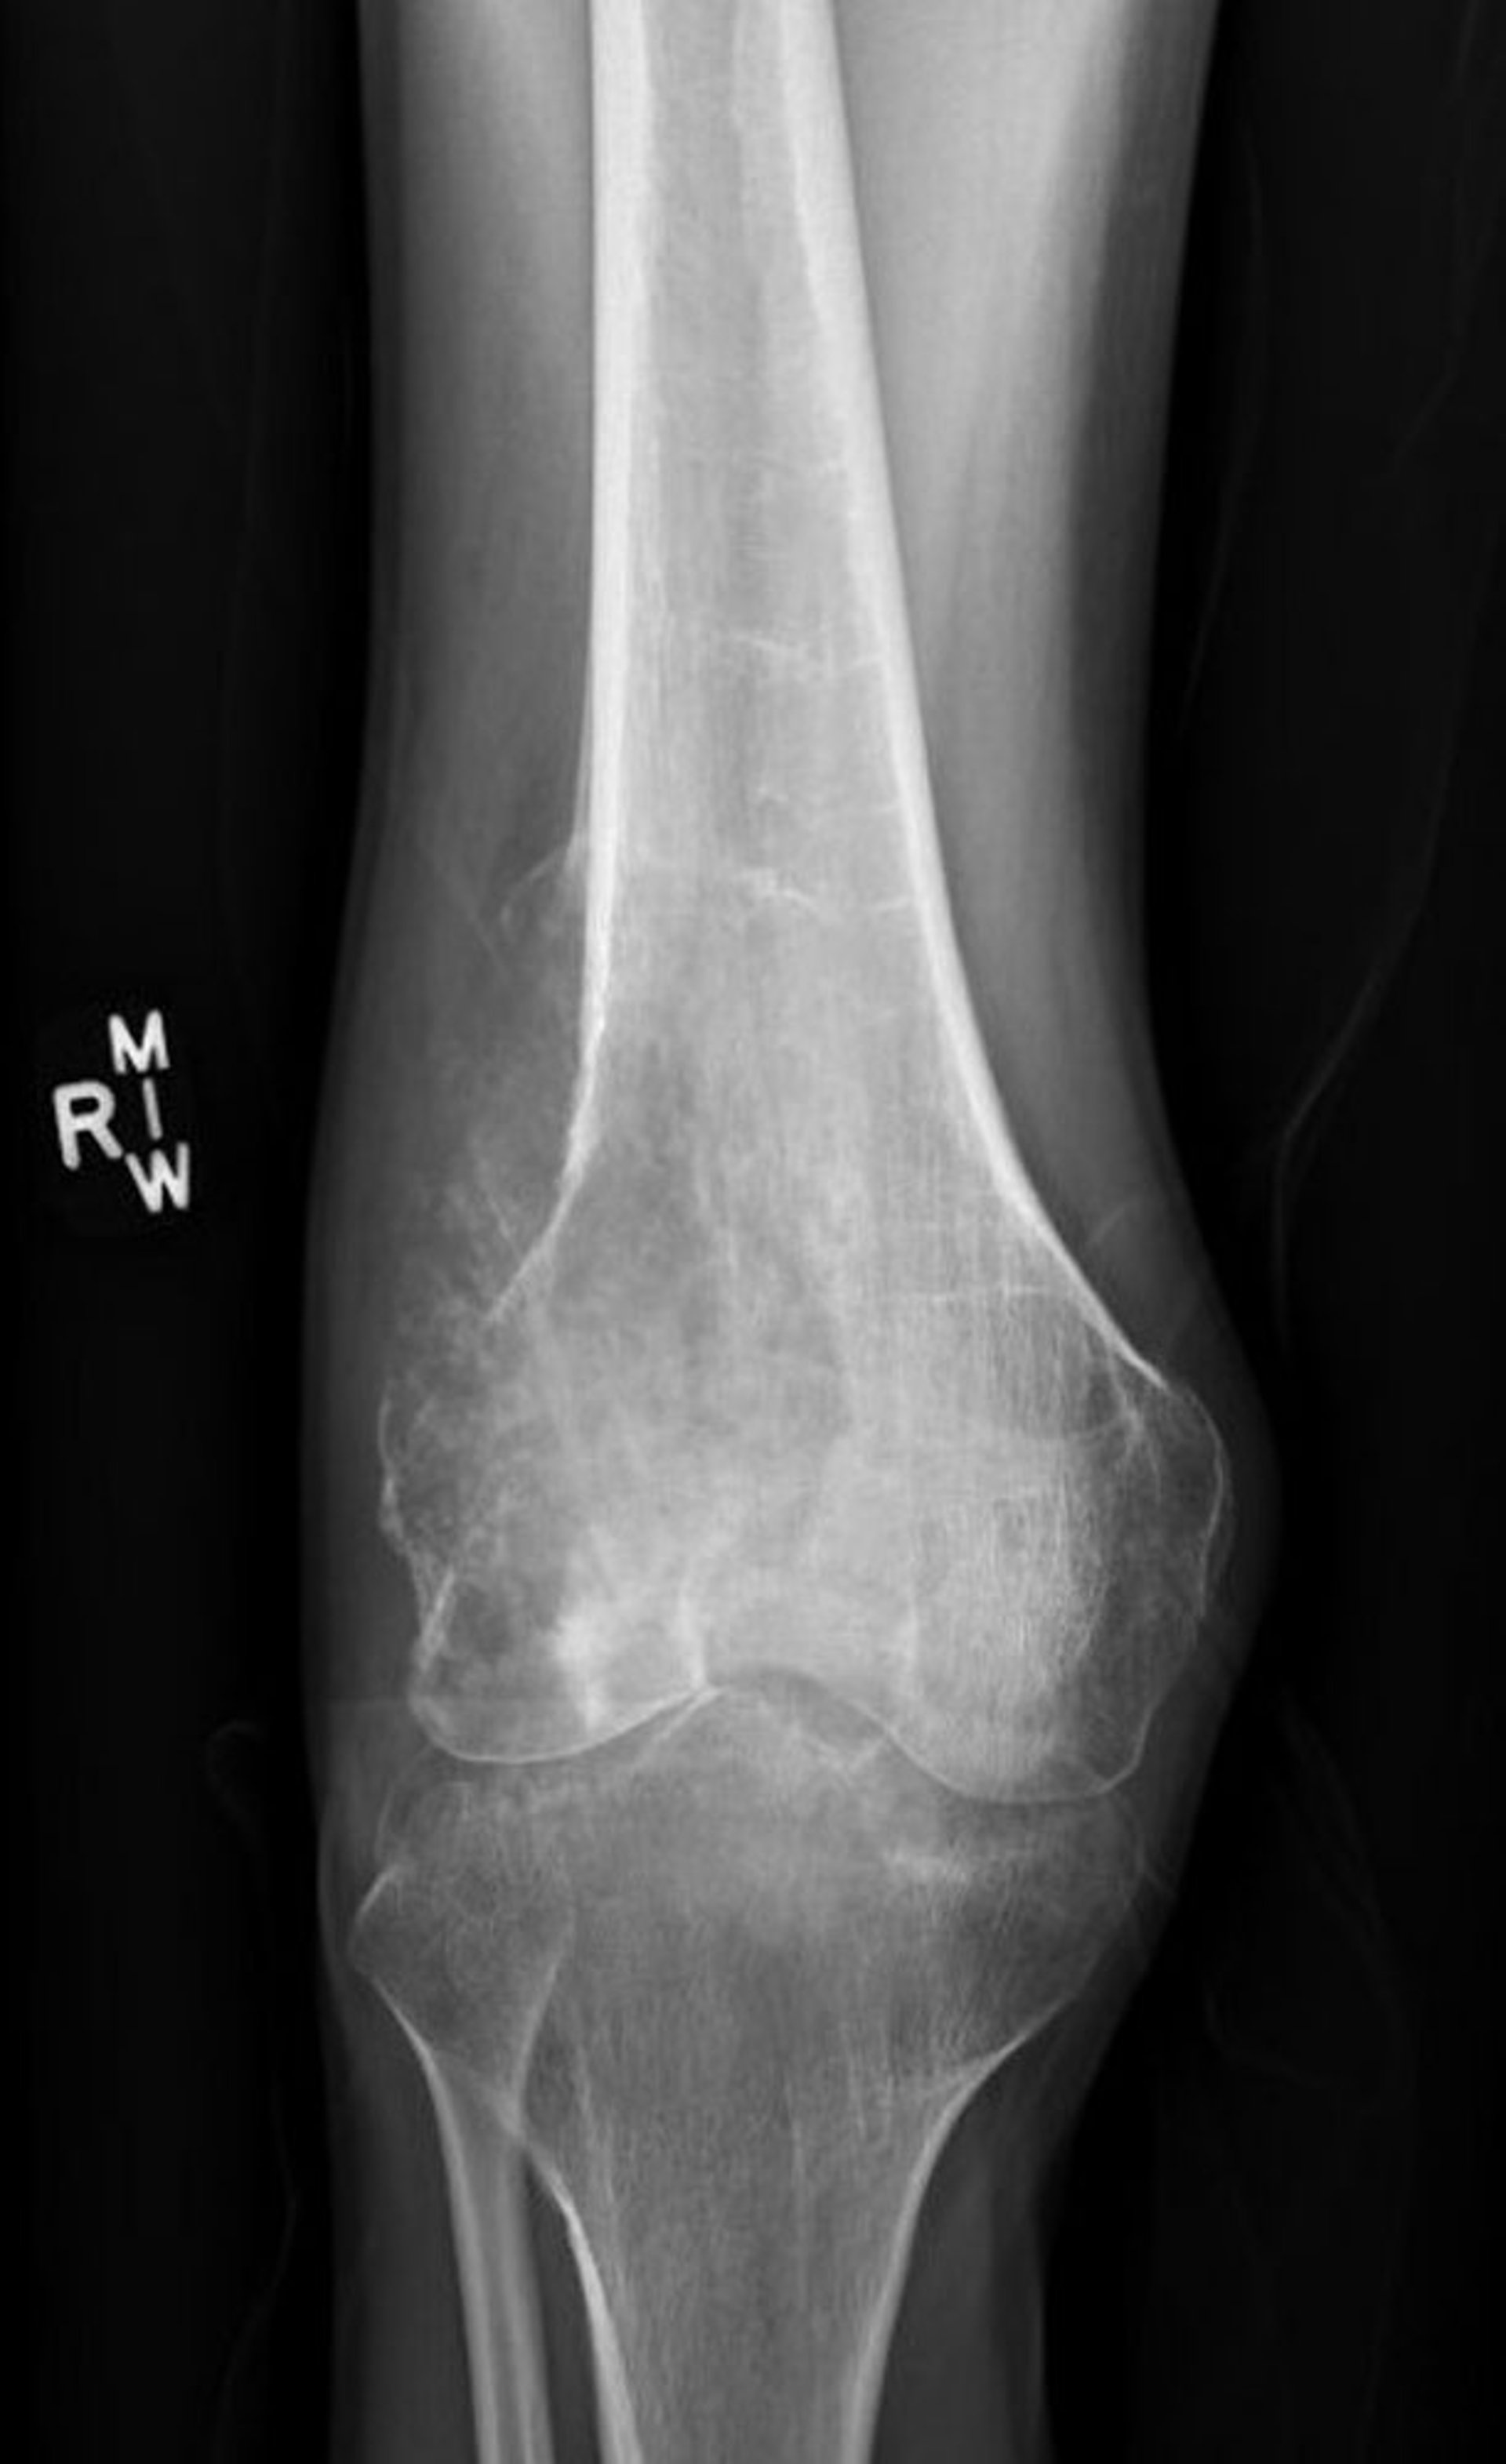

Ostéosarcome

Cette radiographie du genou montre un ostéosarcome destructeur du fémur au-dessus du genou, à aspect lytique destructeur, avec un triangle de Codman classique montrant un soulèvement périosté pathologique.

Image courtesy of Lukas Nystrom, MD.